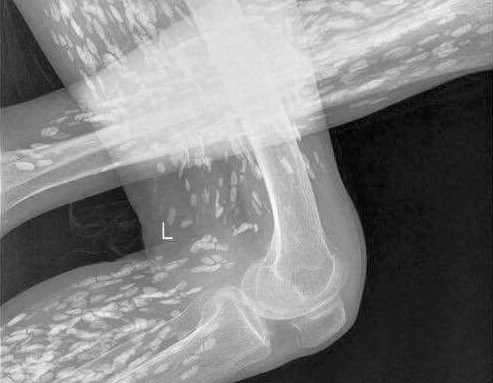

Hình ảnh chụp X- Quang bệnh nhân Th. cho thấy trùng sán dây đã chạy khắp cơ thể bệnh nhân với mật độ dày đặc.

Mới đây, bệnh viện Trung ương Thái Nguyên vừa tiếp nhận trường hợp bệnh nhân Nguyễn Thị Th. (69 tuổi) trú tại Đồng Hỷ - Thái Nguyên nhiễm sán dây. Bệnh nhân nhiễm sán dây do ăn tiết canh và nhập viện vào ngày 26/9/2016.